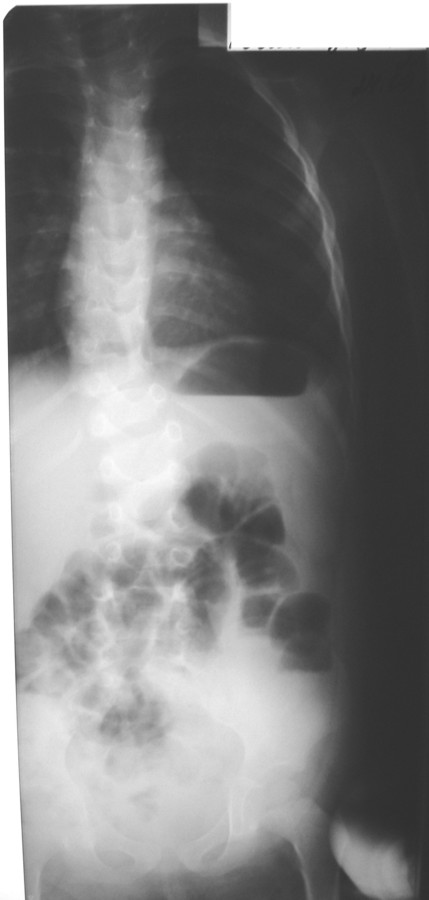

При осмотре: определяется – перекос таза вправо, S–образное искривление позвоночника, ассиметрия надплечий, треугольников талии, правосторонний мышечный валик в поясничном отделе позвоночника.

На рентгенограммах с 1 грудного по 1 крестцовый (прямая проекция) – аномалия развития позвоночника: левосторонний клиновидный позвонок 3 грудного, правосторонний клиновидный позвонок 11 грудного. Добавочный левосторонний клиновидный позвонок между 2 поясничным и 3 поясничным S-образный с ротацией тел. Перекос таза вправо.